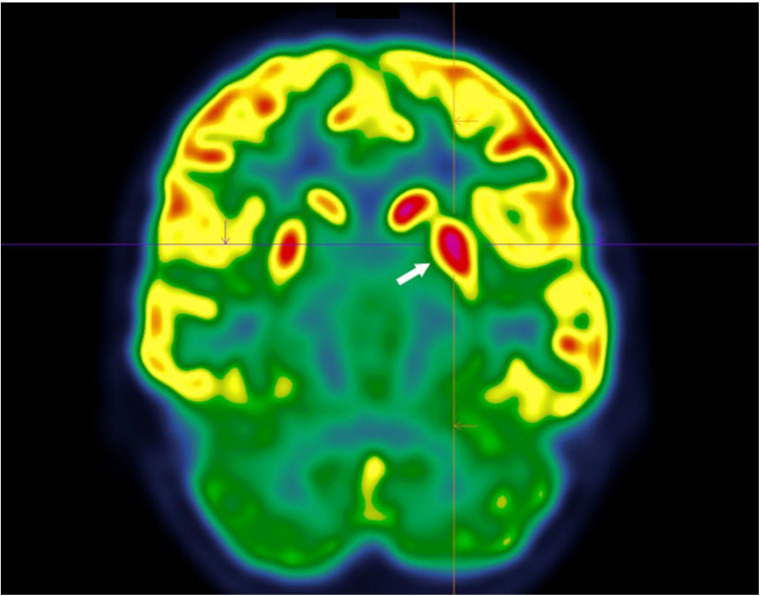

Sydenham's chorea is an autoimmune reaction against cerebral basal ganglia associated with rheumatic fever, caused by group A beta-hemolytic streptococcus infection. Diagnosis of this condition is difficult because of significant delay between infection onset and symptoms presentation, resulting in few positive biological tests or imaging exams. We report the case of a nine-year-old boy exhibiting hemicorporal abnormal movements with tics for whom [18F]FDG PET/CT exam allowed to make the diagnosis, associated with anti-DNase B elevation. Other biology, spinal tap, EEG and imaging modality like MRI or scanner, were non-contributory.